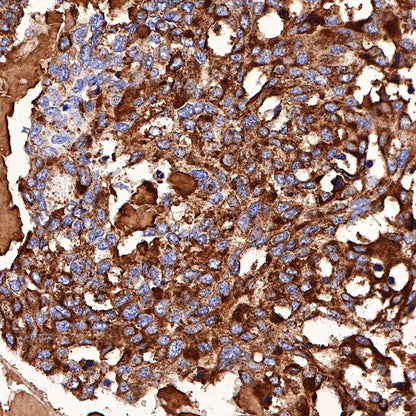

Immunohistochemistry

IHC shows positive staining in paraffin-embedded human medullary thyroid carcinoma. Anti-Calcitonin antibody was used at 1/1000 dilution, followed by a HRP Polymer for Mouse & Rabbit IgG (ready to use). Counterstained with hematoxylin. Heat mediated antigen retrieval with Tris/EDTA buffer pH9.0 was performed before commencing with IHC staining protocol.